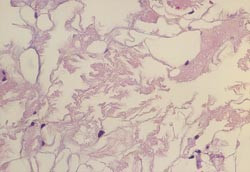

Beincystene er fylt med delvis nekrotisk fettvev og inneholder to komponenter:

• – Cysterom fylt med triglyserider

• – Eiendommelige 1 – 2 µ m tykke, foldede og ultrastrukturelt karakteristiske, autofluorescerende membraner i dobbelt lag

Membranene og de laminære strukturer består av karbohydrater, lipider og fosfolipider (10) som omgir fettsyrekrystaller, hydroksyapatittkrystaller og kollagenholdig bindevev.

I sentralnervesystemet består de makroskopiske anomalier i atrofisk sklerose av hvit substans, mest uttalt i frontal- og temporalregionen. Det er kun beskjeden affeksjon av cortex. Mikroskopisk finnes generalisert demyelinisering, markert fibrillær gliose, aksonal degenerasjon med sferoider og leilighetsvis calcosferitter i basalgangliene.